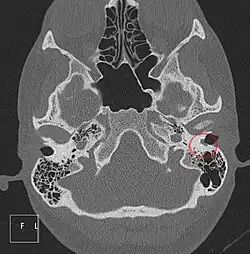

Axiale CT, Cholesteatom im linken äußeren Gehörgang (rechts im Bild). Die Computertomographie zeigt eine kleine, weichteildichte Arrosion des Knochens.

Computertomographie-Serie eines Cholesteatoms (im Bild rot) im Kuppelraum des Mittelohrs